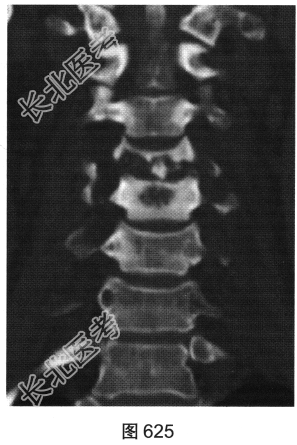

- [材料题] 患者男性,34岁,近数月乏力,偶有低热。颈部疼痛2个月余,逐渐加重,有轻压痛,颈部活动受限。

- 多项选择题2.[提示]患者行颈椎X线、CT和MRI检查,见图623~图628。首先应考虑患者为下列哪种疾病( )

A、淋巴瘤

B、骨髓瘤

C、颈椎退变

D、颈椎结核

E、化脓性颈椎炎

F、转移瘤